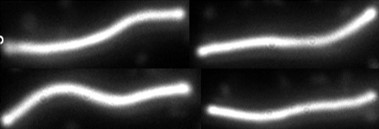

A Lyme borreliosis, azaz a Lyme-kór világszerte a leggyakoribb állatról emberre terjedő fertőzés, és egyben a leggyakoribb kullancs által terjesztett bakteriális megbetegedés. A betegség kórokozója a Borrelia burgdorferi nevű baktérium: egy igen mozgékony, hullámos alakú, Borrelia genusba sorolt baktérium, egy Spirochéta, ami kb. 15 mikrométer hosszú és 0,2 mikrométer széles. Teflon-parazitának is emlegetik, mert felszínét különleges anyag burkolja, kevés rajta a felszíni antigén, ezért ahhoz alig kapcsolódhat a szervezetet védő ellenanyag. Kezelés nélkül évekig évtizedekig megbújhat a szervezetben. Ez rendkívüli alkalmazkodása és kiváló védekezőképessége mellett vegetatív alakjainak, az ún. gemmáknak is köszönhető.